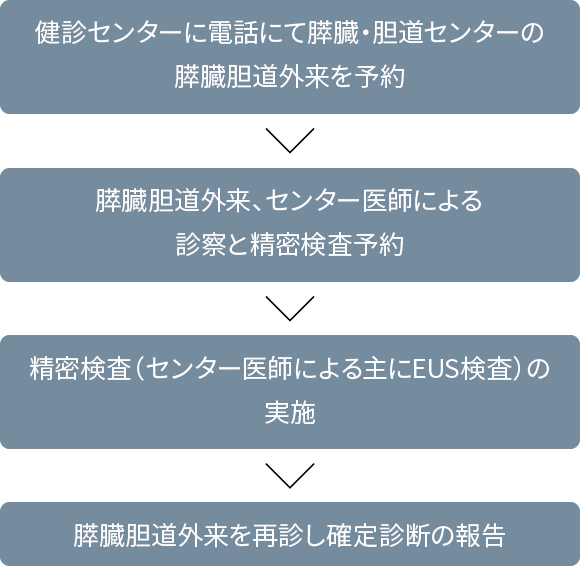

申し込みは下記にお電話いただくか、直接健診センターで受け付けております。

(申込み時に簡単な問診を行います)

電話:025-552-8835 健診センター 膵がん・胆道がんドック予約担当

(受付時間:午後1:00~午後4:00 *土日祝祭日を除く)

問診、採血、MRI、により膵がん、胆道がんの可能性のある方をスクリーニングします。

17,600円(税込)

(糸魚川市民の45歳以上の方には、糸魚川市より半額の補助が出ます。申し込み時にお申し出ください。)

(1日1名の予約枠です)